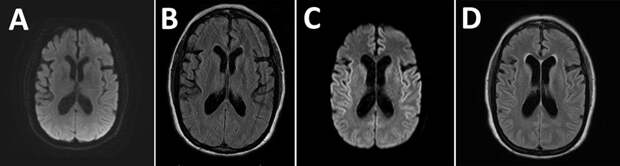

МРТ пациентки: А,B — в начале появления симптомов, C,D — через два месяца

В связи с ухудшением состояния пациентка снова попала в больницу. Дело приняло такой серьезный поворот, что уже в больнице ее сознание и дыхание стали угасать, в связи с чем была проведена интубация. И вот через два месяца после первого МРТ на повторном были найдены нарушения, как и в анализах крови, но главное – у женщины был выявлен повышенный уровень тау-белка и белка 14-3-3, другие анализы также выявили наличие прионов. Как пациентка ранее просила, интубация была прервана, и она умерла.Посмертно с помощью биохимических и патологоанатомических исследований женщине поставили диагноз — болезнь Крейтцфельдта-Якоба. Более того, у женщины была найдена форма гена PRNP, кодирующего прионный белок, которая ассоциирована с длительным латентным периодом заболевания. Источник приона был определен однозначно – гормон роста (более 250 человек в мире заразились прионом именно через человеческий гормон роста). Специфические оценки показали, что заражение женщины прионами произошло примерно 48 лет назад.